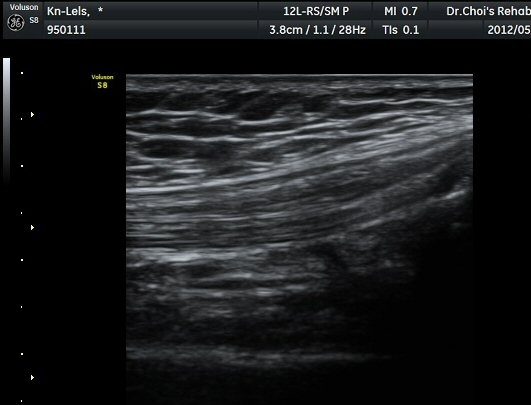

½½°³°ñ¾Æ·¡ ÈûÁÙ Á¾´Ü¸é°Ë»ç¿Í Ⱦ´Ü¸é°Ë»ç¿¡¼­ ÈûÁÙÀÇ ºñÈİ¡ °üÂûµÇ°í(±×¸² 3, 4).

ÈûÁÙÀÇ ºñÈÄ´Â °ÇÃø(±×¸² 5)°ú ºñ±³ÇÏ¸é ¶Ñ·ÈÇϰí, ÆÄ¿öµµÇ÷¯°Ë»ç¿¡¼­ ÈûÁÙ³»¿¡

Ç÷·ùÁõ°¡µµ È®ÀδϵȴÙ(±×¸² 6, 7).